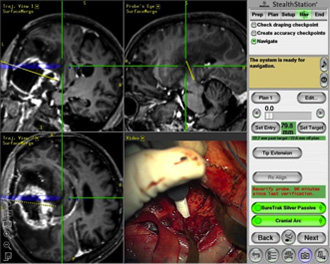

1.ニューロナビゲーション Neuronavigation

脳腫瘍の位置を手術中に知ることが出来ます。同時に脳の重要な機能部位もわかりますので、それらを損傷しないように手術を行うことが出来ます。